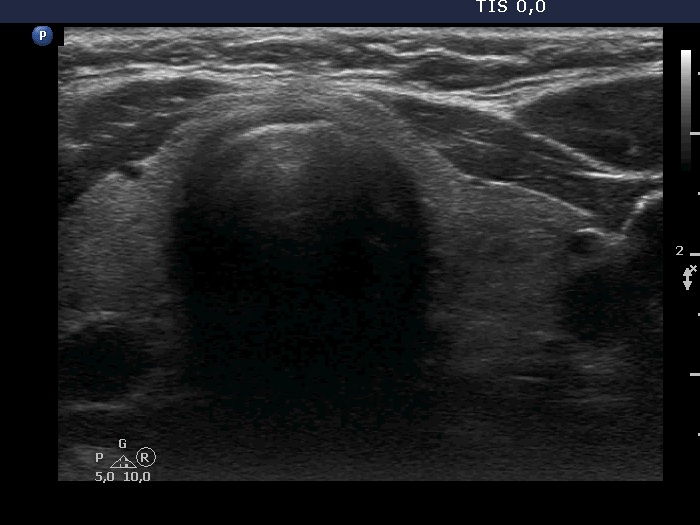

Right lobe, longitudinal scan

Left lobe, transverse scan. This lobe has a minimally hypoechoic lesion in the central part.